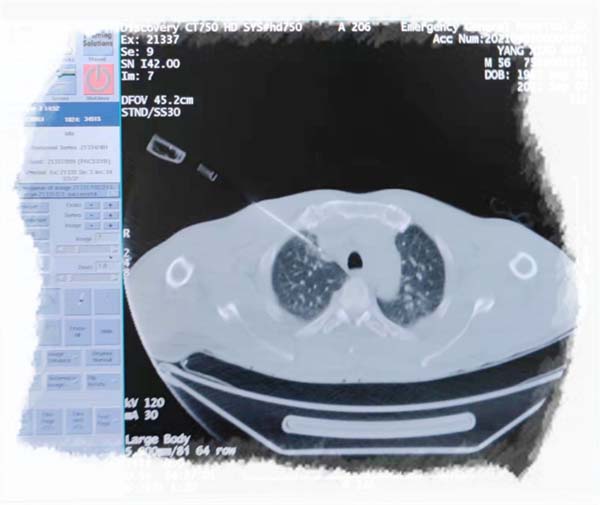

肺结节是边界清楚的、影像学不透明的、直径≤3cm的局灶性、类圆形、密度增高的实性或亚实性肺部阴影。

近年来随着低剂量 CT 筛查的人群日益增长,筛查出的肺结节病例显著增加。如果体检中发现肺部结节或小结节,不要过度惊慌,但也不要太过忽视,应及时就诊。

肺部结节未必就是恶性肿瘤,可能是由各种病原体导致肺炎或肺结核引起的良性结节,对于结节性质要做专业的鉴别诊断及专业随诊。而对于恶性肿瘤引起的肺部结节,应早诊早治,可以通过手术治疗或抗肿瘤药物治疗来避免肿瘤的进展,但治疗时机及治疗方案应对专业规划。CT上的高危结节包括:直径≥15 mm或表现出恶性CT征像(分叶、毛刺、胸膜牵拉、含气细支气管征和小泡征、偏心厚壁空洞)的直径介于8 mm-15 mm之间的肺实性结节。直径>8 mm的部分实性结节定义为高危结节,尤其有吸烟史的患者尤其应加以警惕。

医生会根据患者的具体情况应用相应的检查手段,如低剂量CT、AI辅助诊断系统、多学科会诊,必要时通过经皮穿刺、经支气管镜等方式进行病理活检,以及同步活检、手术切除等方法。